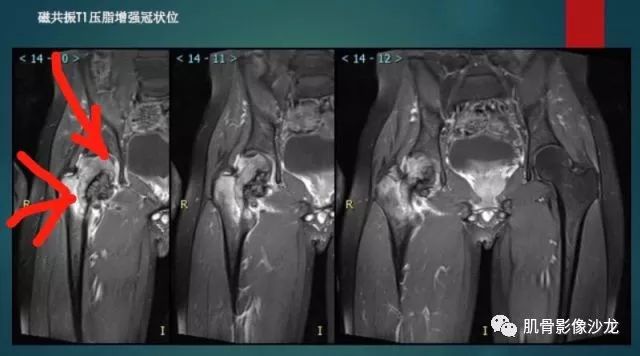

主诉:右髋及右膝部疼痛3月余

现病史:3月前打球时自觉右大腿肌肉拉伤后右髋及右膝部疼痛,自服“活血化瘀”类药物(具体不详)后自觉疼痛缓解,2月前打球时再次扭伤,右髋及右膝部疼痛明显,行走时疼痛加重,自服药物治疗,效果不佳,遂来诊。

葛英霖 20:10 判断恶性程度需要看骨髓内浸润的是肿瘤还是水肿 ,从目前看,骨肉瘤是要考虑的

张小林 20:13 磁共振有双低信号,结合CT确实要考虑有纤维成份。

医影在线 20:13 干骺端溶骨性破坏,边缘模糊,低密度肿块,似有钙化

Echo 20:13 有骨质破坏,边界不清,有软组织肿块,我觉得恶性是要考虑的

Echo 20:23 我个人觉得,17岁男性,病灶发生在原干骺端区域,溶骨性骨质破坏,似有肿瘤骨,有软组织肿块形成,从常见病发生率来说,骨肉瘤还是要考虑的

葛英霖 20:37 明显侵蚀骨内膜啊,硬化边也不完整 (细箭头所示)